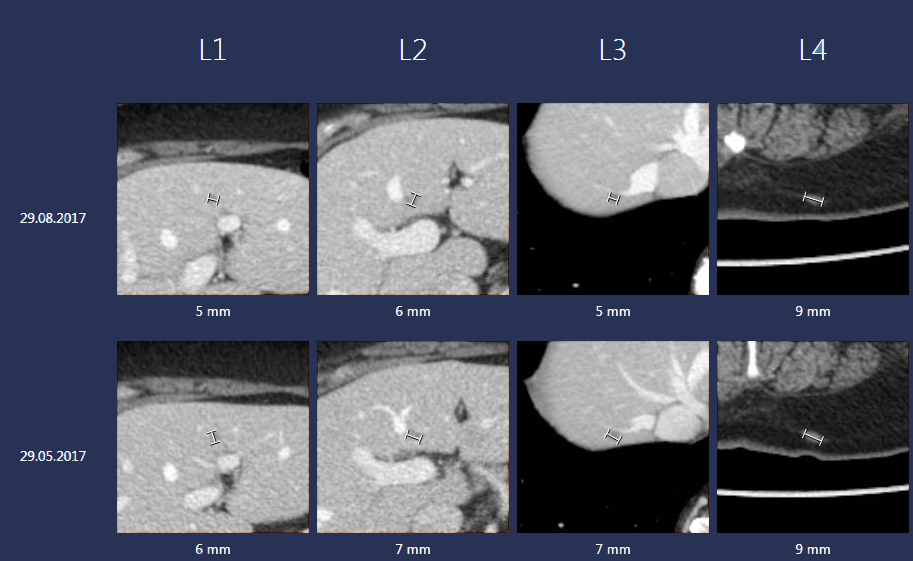

The SLT tool was determined to be more efficient the more prior exams the patient had. The time saved was also determined to be greater for patients with more than one lesion. This is because SLT creates a library of lesion snapshots to give an easy overview, as shown in image 1. Note that all cases were assessed to be complex cancer cases.

A screenshot of the Sectra Lesion Tracking tool

Image 1. A screenshot of the Sectra Lesion Tracking tool showing measurements of four lesions at two different timepoints.